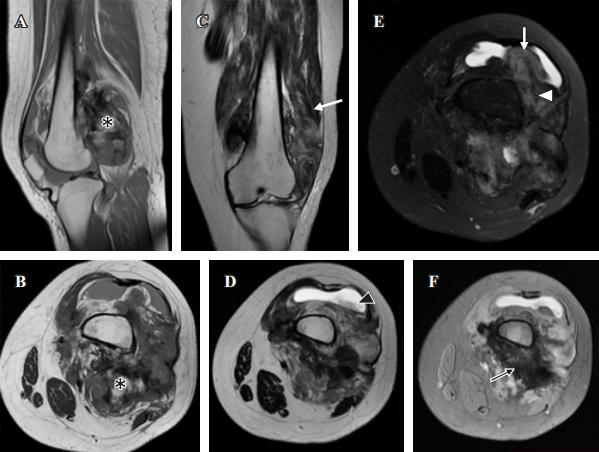

磁共振显示为异质性肿瘤,在MRI所有序列中均有大面积低信号强度,与脂肪行为区和中等强度区交替(图3)。

图3、核磁共振

(A y B) T1矢状和轴状

(C y D) T2冠状和轴状

(E) T2与冠状动脉脂肪饱和度

(F)轴向面梯度回波